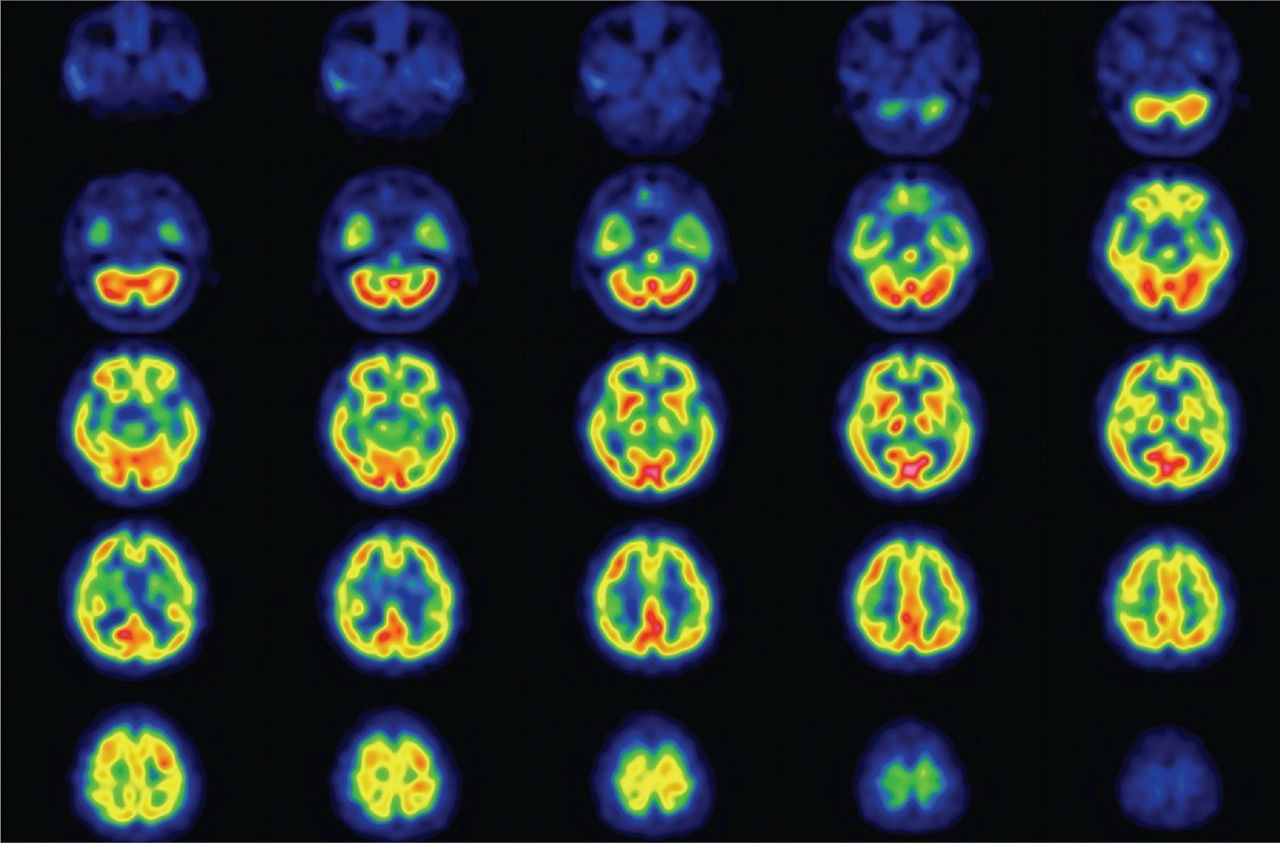

CZT: Precision Imaging at the Speed of Tomorrow

brain-scan-ci-en

Changing the way we see the world